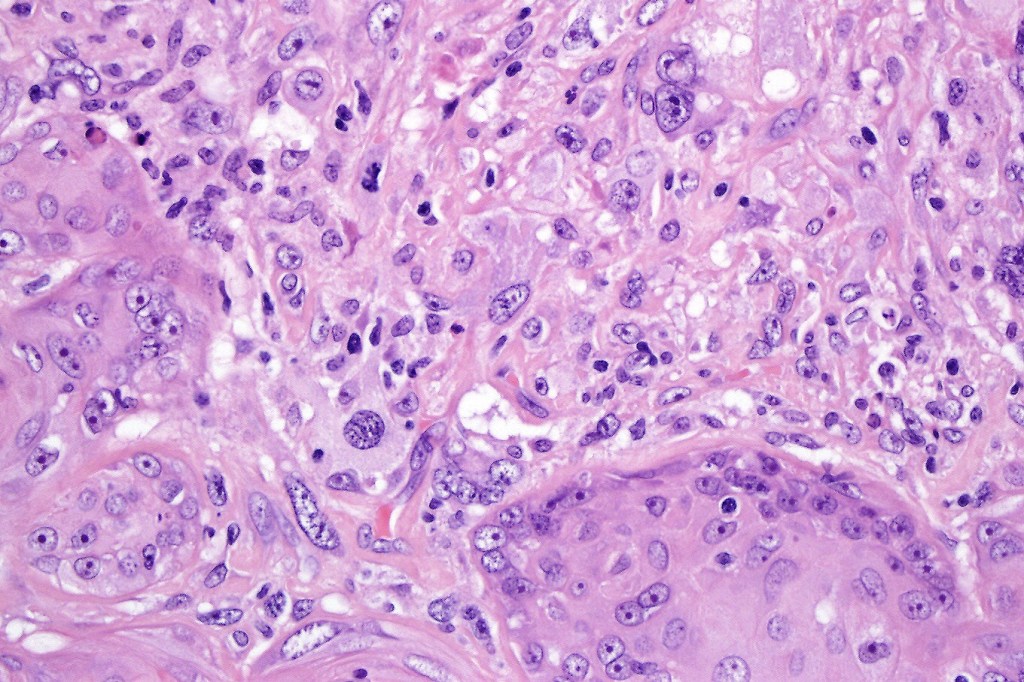

•Biphasic tumor

•Admixture of squamous carcinoma & pleomorphic spindled cell, osteoid, chondroid, MFH-like +/- osteoclast-like giant cells & rarely, smooth muscle, skeletal muscle, myofibroblastic or angiosarcomatous elements

•Epithelial component AE1/AE3, CK5/6 & p63 +ve;

•Mesenchymal element variable CD10, CD68, CD99 & lineage specific markers +ve; scattered cells may show weak keratin expression